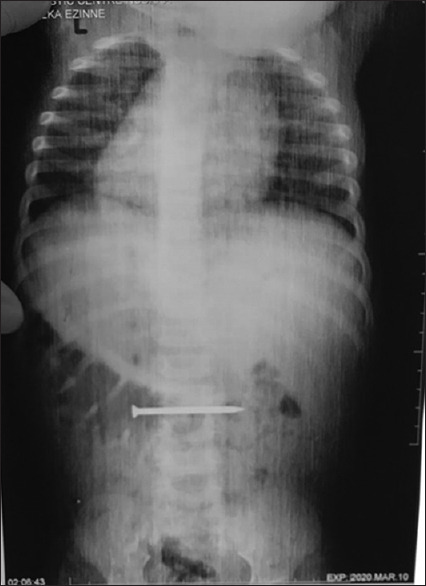

Results: A total of 272 children presented with FB in the GIT during the study period, out of which 30 patients had laparotomy. This gave an operative incidence rate of 11%. There was a slight male predominance and the ages of the patients ranged from 6 months to 5 years (median 3 years). About half of the patients had no symptoms and all the patients were investigated with an abdominal radiograph. Only one-third of the patients had a predisposing factor that could have led to FB impaction. FB impaction was the most common indication for surgery, and enterotomy with FB removal was the most performed surgical procedure. The most common FB removed were tiny parts of toys, and the most common post-operative complication was surgical site infection. There was no mortality.